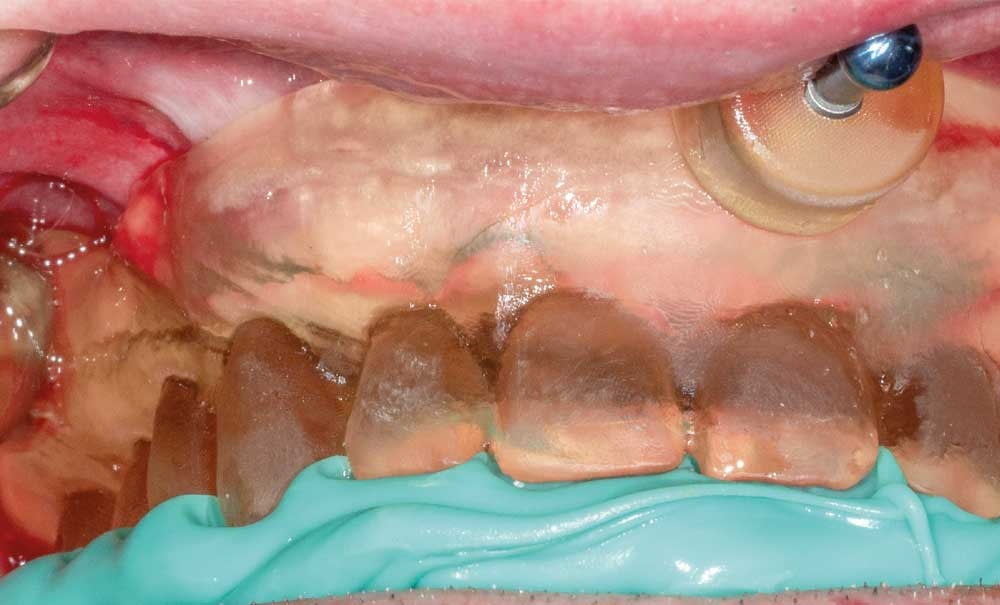

Les protocoles de mise en charge immédiate chez le patient édenté ont fait leurs preuves, et l’on retrouve de nombreuses publications validant cette approche, tant à la mandibule qu’au maxillaire [1]. L’apport de la chirurgie guidée est indéniable dans ce type de thérapeutique tant du point du chirurgien (en termes de précision, de reproductibilité) que du point de vue du patient (en termes de confort) [2]. Ces dix dernières années, ces protocoles n’ont fait qu’évoluer sous l’influence de l’arrivée de nouveaux outils numériques dans nos cabinets (empreinte optique, CBCT, scanner facial…). Nous présentons dans cet article un cas de mise en charge immédiate (MCI) mêlant flux digital et approche conventionnelle réalisé selon le protocole Dual-Scan CT proposé par le logiciel de planification implantaire Implant studio (3Shape).

Ce protocole bien connu permet, à partir d’une prothèse complète existante, de réaliser une planification implantaire et de générer un ou plusieurs guides chirurgicaux pour la mise en place d’implants en chirurgie guidée. Cependant, une fois les implants placés, malgré cette approche numérique, la charge de travail pour le prothésiste en vue de la MCI est toujours aussi importante si l’on s’en tient à la procédure classique de transformation de la prothèse totale en prothèse fixe transitoire implanto-portée [3-5].